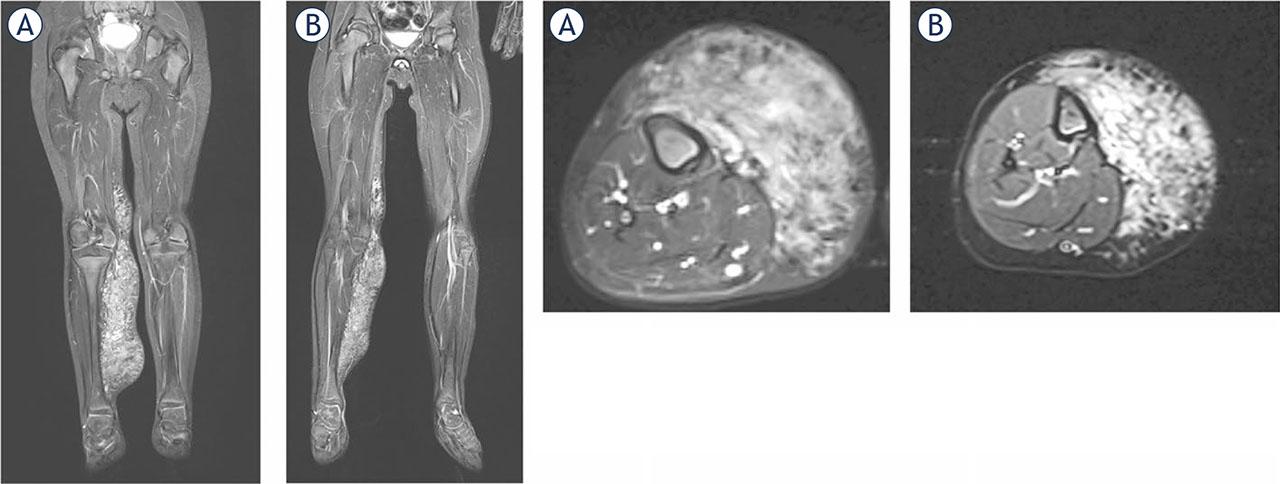

Magnetic Resonance Imaging (MRI) in most cases prior to interventional treatments to fully define and assess the low flow malformation (extent, deeper parts, drainage, differential diagnosis, multifocal lesion, etc.)

The Current Operating Procedure (COP) for Bleomycin ElectroScleroTherapy (BEST), as outlined in this article, represents the first consensus-driven protocol for the treatment of low-flow vascular malformations. Multiple centers across Europe and the United Kingdom practice BEST, having acquired their skills either through treating tumours with electrochemotherapy—where standard operating procedures (SOPs) are already established—or by training under specialists in this field.23 This article summarizes the collective experience in a concise list of steps recommended to maximize safety and clinical effectiveness based on current knowledge (Figure 3, 4) The COP was initially developed by a small group of authors and subsequently reviewed and refined by a broader community of co-authors, ensuring comprehensive consensus within the BEST community. As most BEST applications have so far focused on treating low-flow vascular malformations, this COP is specifically tailored to this type of malformation. We anticipate that future iterations of the COP will evolve into SOPs based on more extensive evidence, ultimately facilitating the wider use and acceptance of BEST for both low-flow and high-flow vascular malformations.